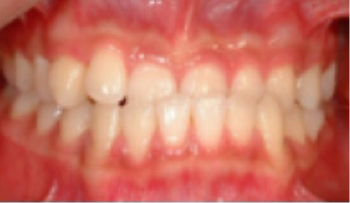

• 치간공극 치아 사이가 벌어짐.

Before

After